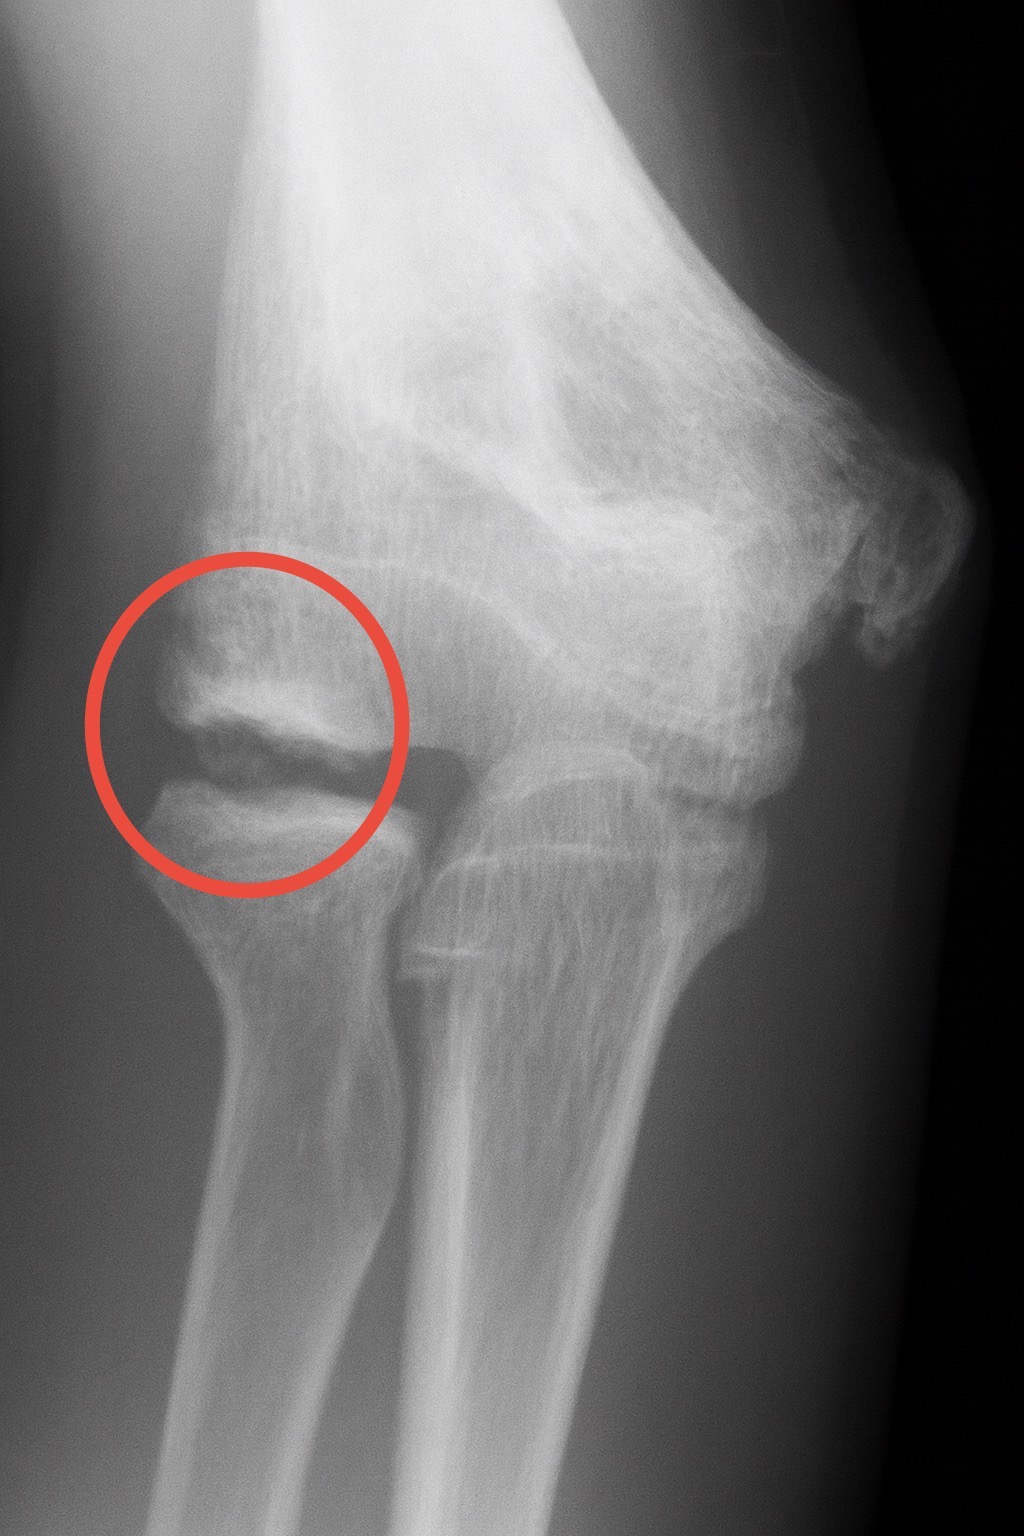

レントゲンではどのように写るの?

レントゲン上では上記画像の赤丸部分の上腕骨小頭という所が下の骨(橈骨)とぶつかる事で骨(軟骨)が剥がれてしまいます。初期の段階であればスポーツ(投球動作)を中止し、悪化を防ぎますが大きく離開してしまう様な場合は手術にて骨を固定します。